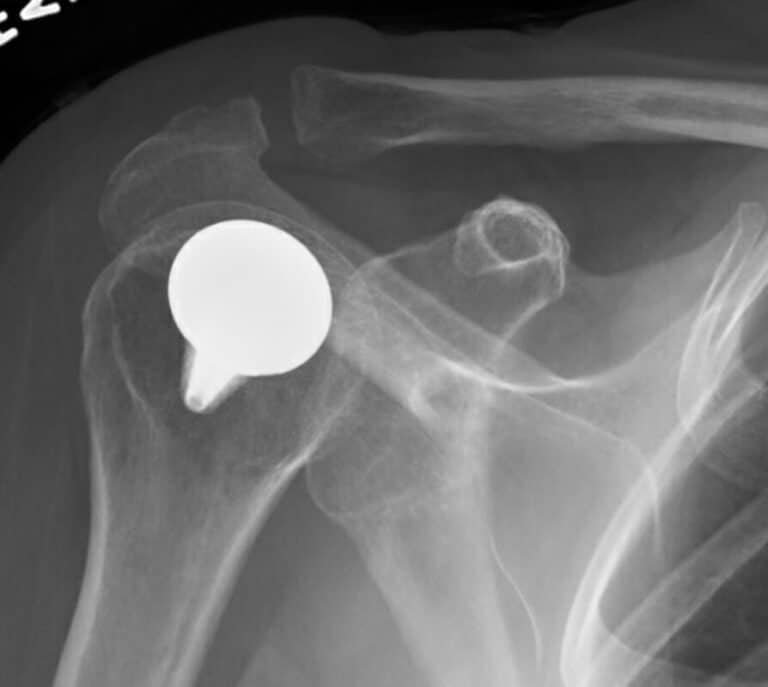

Arthrosurface, HemiCap Small